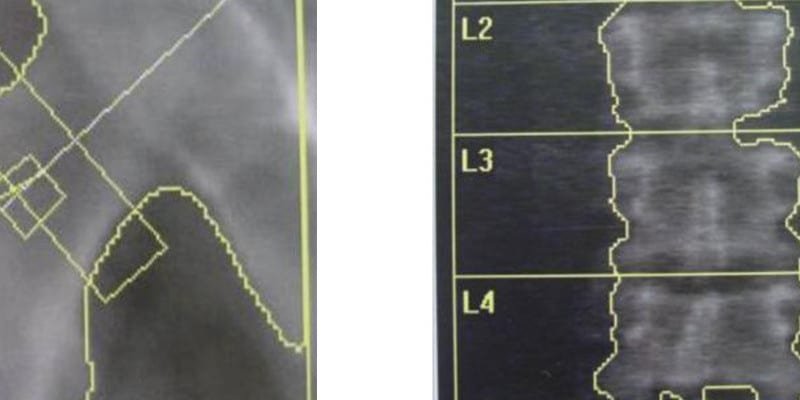

One of the complications in patients with chronic kidney disease (CKD) is increased bone turnover and decreased bone mineral density. Bone mineral density (BMD) indicates bone mass and bone mineral content. It is measured using dual-energy x-ray absorptiometry (DEXA) scans at both the posteroanterior lumbar spine (L1-L4) and the hip (femoral neck or entire proximal femur). Previous meta-analyses highlighted a significant association between CKD and low BMD increasing fracture risk. Currently, there is conflicting evidence regarding DEXA scan measurements and biochemical markers of osteopenia and osteoporosis. In this cross-sectional study, researchers aimed to determine the prevalence in patients undergoing peritoneal dialysis (PD) and to correlate related biochemical variables. Patients undergoing PD were evaluated for clinical characteristics, biochemical markers, and BMD. A vitamin D survey showed that 86.8% of participants were deficient, with a median value of 8.7 ng/mL. BMD measurements revealed a 41% prevalence of osteoporosis at the femoral neck and 38% at the lumbar spine. Multivariate analysis examining the correlation between 25-vitamin D levels and BMD did not show a significant correlation. However, another multivariate analysis showed that BMI was positively correlated with BMD at both the femoral neck and lumbar spine. Clinical and biochemical markers of osteoporosis need to be further investigated to promptly initiate osteoporosis treatment in PD patients. Prophylactic vitamin D supplementation should be considered in PD patients.

Image: PD